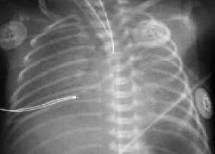

Снижение пневматизации легких, воздушные бронхограммы, границы сердца на рентгенограмме ещё различимы (Рис.5).

Рисунок 5.

РДС. Рентгенограмма в прямой проекции, в горизонтальном положении. Верхние доли легких и средняя доля справа неоднородно слабоинтенсивно затемнены, корни легких расширены, не структурны. Сосудисто-интерстициальный рисунок легких деформирован, усилен, размыт. Тень средостения с нечётким контуром, протекционно смещена влево за счёт подворота. (

Диагностика и лечение РДС недоношенных // метод. рекомендация, 2007)